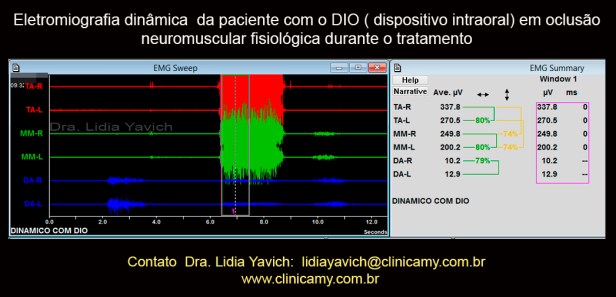

Registro eletromiográfico com o DIO (dispositivo intraoral) em posição neuromuscular fisiológica.

Registro eletromiográfico com o DIO (dispositivo intraoral) em posição neuromuscular fisiológica.

Notasse o maior recrutamento de unidades motoras nos músculos masseteres que anteriormente mostravam pouquíssima atividade.